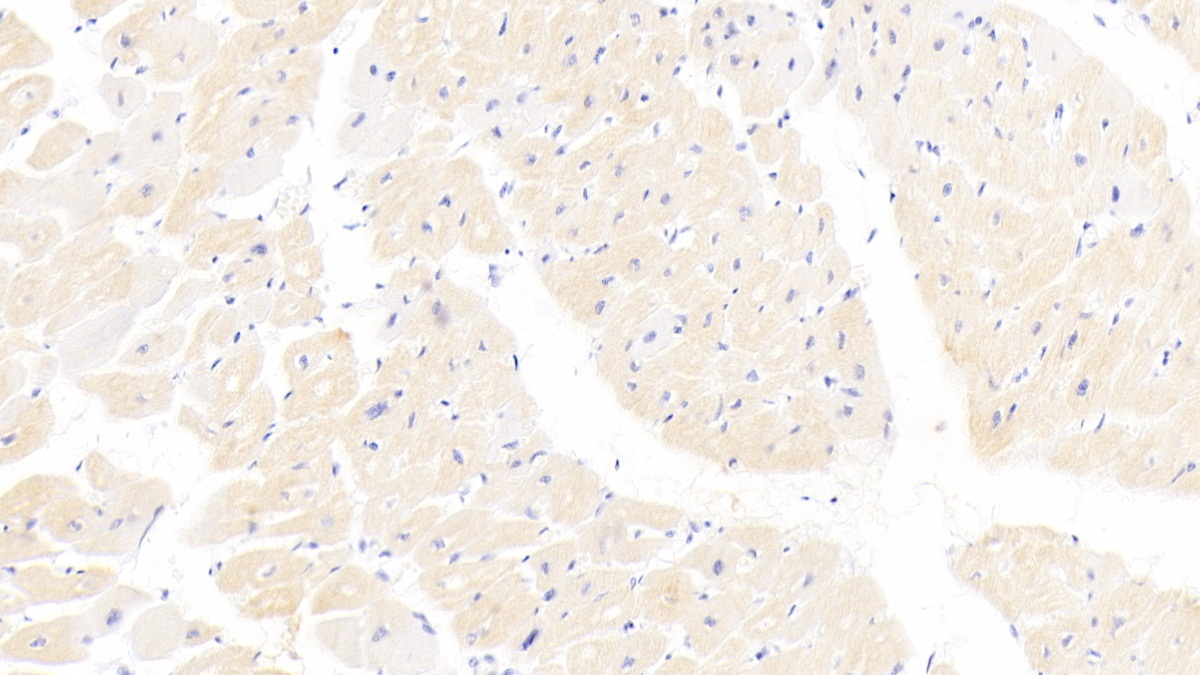

心肌肌钙蛋白I(cTnI)是肌钙蛋白复合体的一个亚基,主要存在于心肌细胞中。它与肌钙蛋白T(TnT)和肌钙蛋白C(TnC)共同组成肌钙蛋白复合体,参与心肌和骨骼肌的收缩调节。cTnI有三种亚型,其中心肌肌钙蛋白I(cTnI)是心肌细胞特有的标志物。

正常情况下,cTnI主要与TnC结合,存在于心肌细胞内,血浆中几乎无法检测到。然而,当心肌因缺血、缺氧而发生损伤时,cTnI会通过受损的细胞膜进入血液循环。研究表明,心肌损伤后3~12小时内,血浆cTnI水平可升高至正常人的5~50倍,并可持续一周或更长时间。这种显著的升高使得cTnI成为检测心肌损伤的灵敏指标。